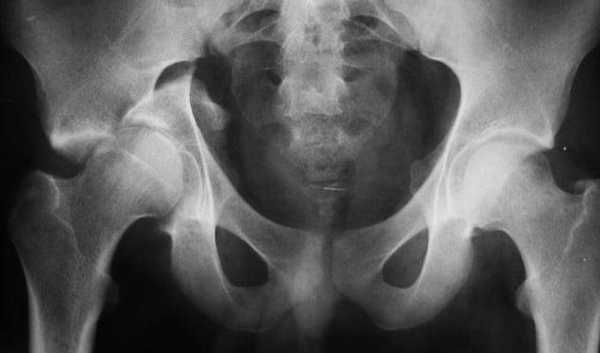

Остеосинтез ТБС на рентгене

Остеосинтез при переломе шейки